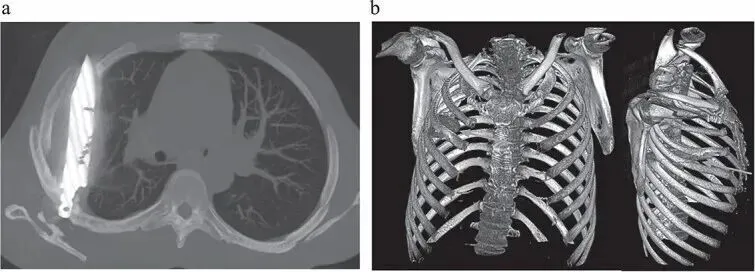

Phim chụp CT (trái) cho thấy lưỡi dao găm vào ngực người đàn ông, trong khi ảnh chụp CT ngực tái tạo 3D (phải) cho thấy cả lưỡi dao và tổn thương xương liên quan mà nó gây ra

Hình ảnh chụp CT cho thấy, mảnh dao đã chui vào giữa khe xương sườn số 5 và 6 từ phía sau, rồi mắc kẹt, đầu nhọn dừng lại ở phía trước giữa xương sườn số 3 và 4. Xung quanh mảnh kim loại, các mô cơ thể đã hình thành bao xơ, giống như cơ chế tự vệ của hệ miễn dịch để “cô lập” dị vật, ngăn ngừa tổn thương lan rộng. Đây chính là lý do bệnh nhân không hề biết trong lồng ngực mình có cả một lưỡi dao suốt ngần ấy năm.